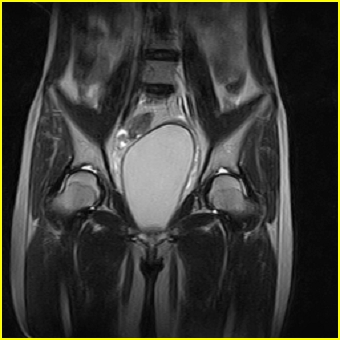

女、15岁、下腹疼痛2天,排尿困难1天。查体:处女膜闭锁,距处女膜约4至5cm处扪及一约5cm直径的圆形包块,张力较高,触痛明显、欠活动。b超提示子宫增大伴宫内增强回声团。

影像意见:子宫直肠陷凹积血。

更正影像意见:阴道积血。

处女膜闭锁,阴道积血

处女膜闭锁,阴道积血,子宫积血.

阴道积血,子宫积血.

子宫及阴道积血。

处女膜闭锁,伴子宫及阴道积血.